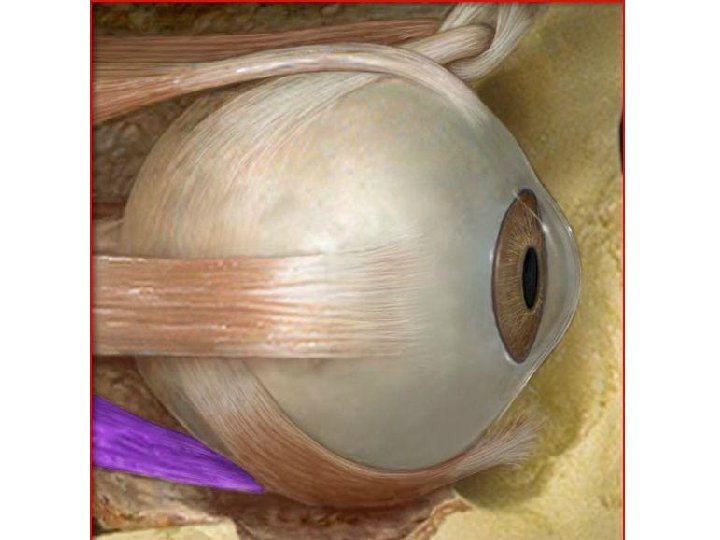

Lateral Rectus Muscle • The agonist of the Medial Rectus Muscle • Moves eye in an outward direction – laterally - away from the nose (Abduction) • Its origin point is the Annulus of Zinn and its insertion point is the Sclera

Medial Rectus Muscle • The antagonist of the Lateral Rectus Muscle • Moves the eye in an inward direction – medially - toward the nose (Adduction) • Its origin point is the Annulus of Zinn and its insertion point is the Sclera

Annulus of Zinn • Fibrous ring located in posterior region of the orbit – around the optic canal • Located around the optic canal and encloses a part of the superior orbital fissure • The common fibrous origin of the 4 recti muscles • Named after Johann Gottfried Zinn

2 Parts of Annulus of Zinn • Upper part – Superior Tendon of Lockwood – Gives origin to superior rectus, part of medial rectus, and upper head of lateral rectus • Lower Part – Ligament/Tendon of Zinn – Gives origin to inferior rectus, part of medial rectus, and lower head of lateral rectus

Superior Rectus Muscle • The agonist of the Inferior Rectus Muscle • Responsible for 2 mvmnts of the eye – Upward (Elevation) – Moves the eye inward (Adduction) • Its origin point is from the Annulus of Zinn • Its insertion point is into the Sclera of the eye

Inferior Rectus Muscle • The antagonist of the Superior Rectus Muscle. • Responsible for 2 mvmnts: – Downward (Depression) – Moves the eye inward (Adduction) • Its origin point is the Annulus of Zinn • Its insertion point is into the sclera of the eye

Superior Oblique Muscle • The agonist of the Inferior Oblique Muscle • Responsible for 2 mvmnts: – Moves eye in downward direction (Depression) – Moves the eye in outward direction (Abduction)

• Its origin point is from the posterior of the Annulus of Zinn • it then passes anteriorly and ends in a round tendon. • The tendon extends through a pulley-like loop of fibrocartilaginous tissue called the trochlea (Pulley) in the anterior medial part of the roof of the orbit • and then turns to its insertion point on the posterolateral aspect of the eyeball.

Inferior Oblique Muscle • The antagonist of Superior Oblique muscle • Responsible for 2 mvmnts – Moves the eye in an upward direction (Elevation) – Moves the eye in an outward direction (Abduction)

• Its origin point is from the maxilla at the anteromedial aspect of the floor of the orbit • its insertion point is on the posterolateral aspect of the eyeball